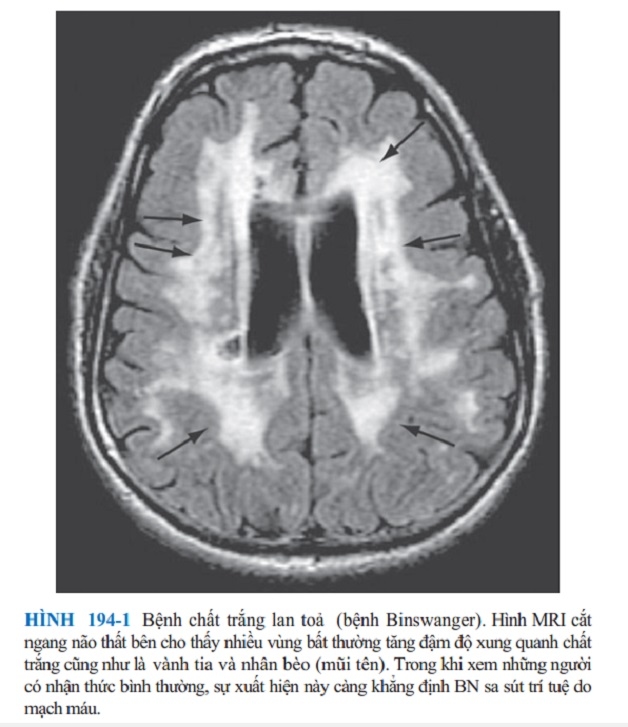

Ngoài Alzheimer, sa sút trí tuệ ở người cao tuổi còn gồm nhiều dạng khác như: sa sút trí tuệ thể Lewy, sa sút trí tuệ do mạch máu, sa sút trí tuệ trán – thái dương,…

Hình ảnh sa sút trí tuệ mạch máu ở người cao tuổi.